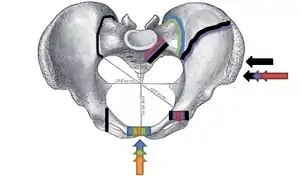

.png.webp)

Pelvic fractures are most commonly described using one of two classification systems. The different forces on the pelvis result in different fractures. Sometimes they are determined based on stability or instability.[8]

Young-Burgess classification

The Young-Burgess classification system is based on mechanism of injury: anteroposterior compression type I, II and III, lateral compression types I, II and III, and vertical shear,[5] or a combination of forces.

Lateral compression (LC) fractures involve transverse fractures of the pubic rami, either ipsilateral or contralateral to a posterior injury.

- Grade I – Associated sacral compression on side of impact

- Grade II – Associated posterior iliac ("crescent") fracture on side of impact

- Grade III – Associated contralateral sacroiliac joint injury

The most common force type, lateral compression (LC) forces, from side-impact automobile accidents and pedestrian injuries, can result in an internal rotation.[9] The superior and inferior pubic rami may fracture anteriorly, for example. Injuries from shear forces, like falls from above, can result in disruption of ligaments or bones. When multiple forces occur, it is called combined mechanical injury (CMI). The best imaging modality to use for this classification is probably a pelvic CT scan.[10]